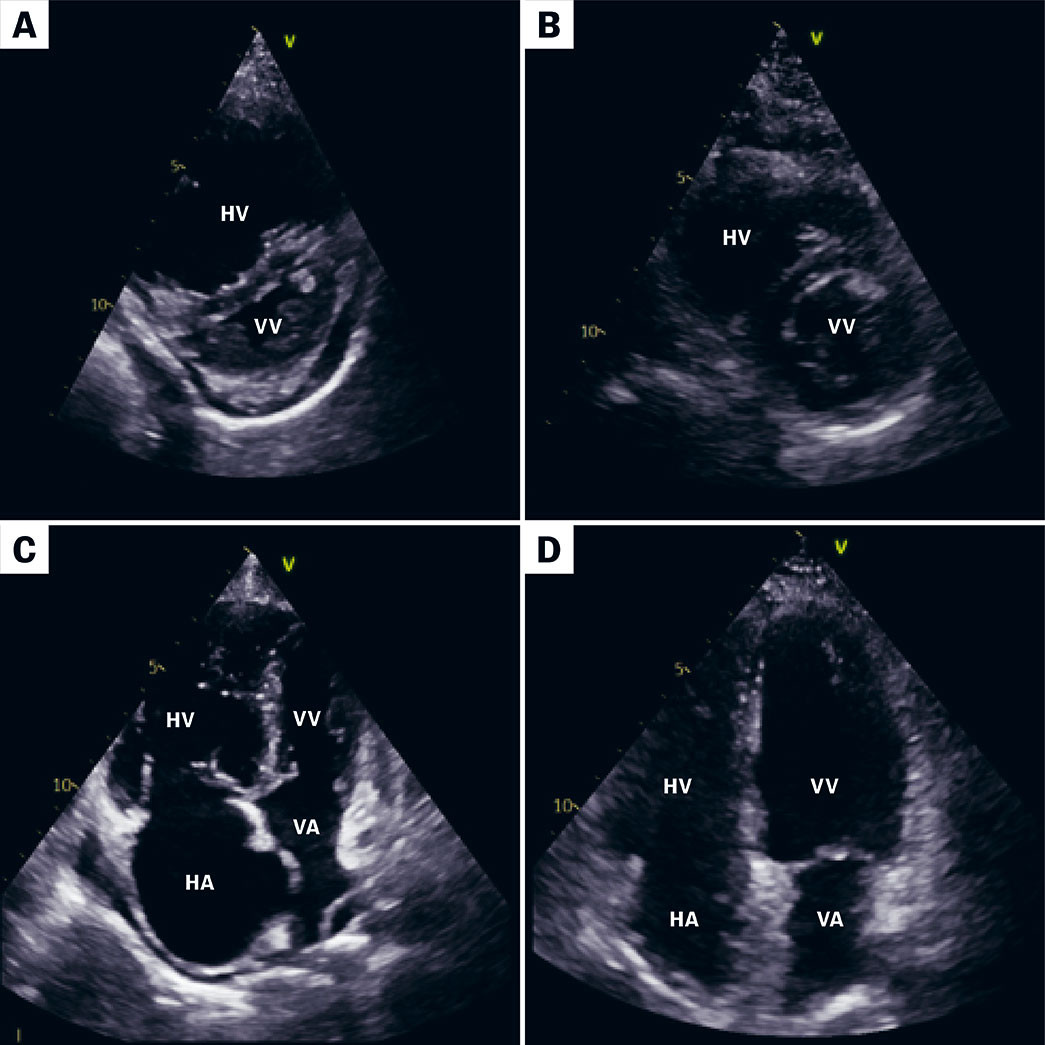

Ved mistanke om tilstanden er ekkokardiografi vanligvis første steg i utredningen. Doppler med hastighetsmåling av trikuspidallekkasjen tillater estimering av trykket i lungearterien. Ved høye trykk ses venstreforskyvning av interventrikulærseptum, redusert fylning av venstre ventrikkel og redusert slagvolum (figur 1). Vedvarende dyspné tre måneder eller mer etter lungeembolisme bør utredes med ekkokardiografi og ved tegn til pulmonal hypertensjon bør man utrede videre.